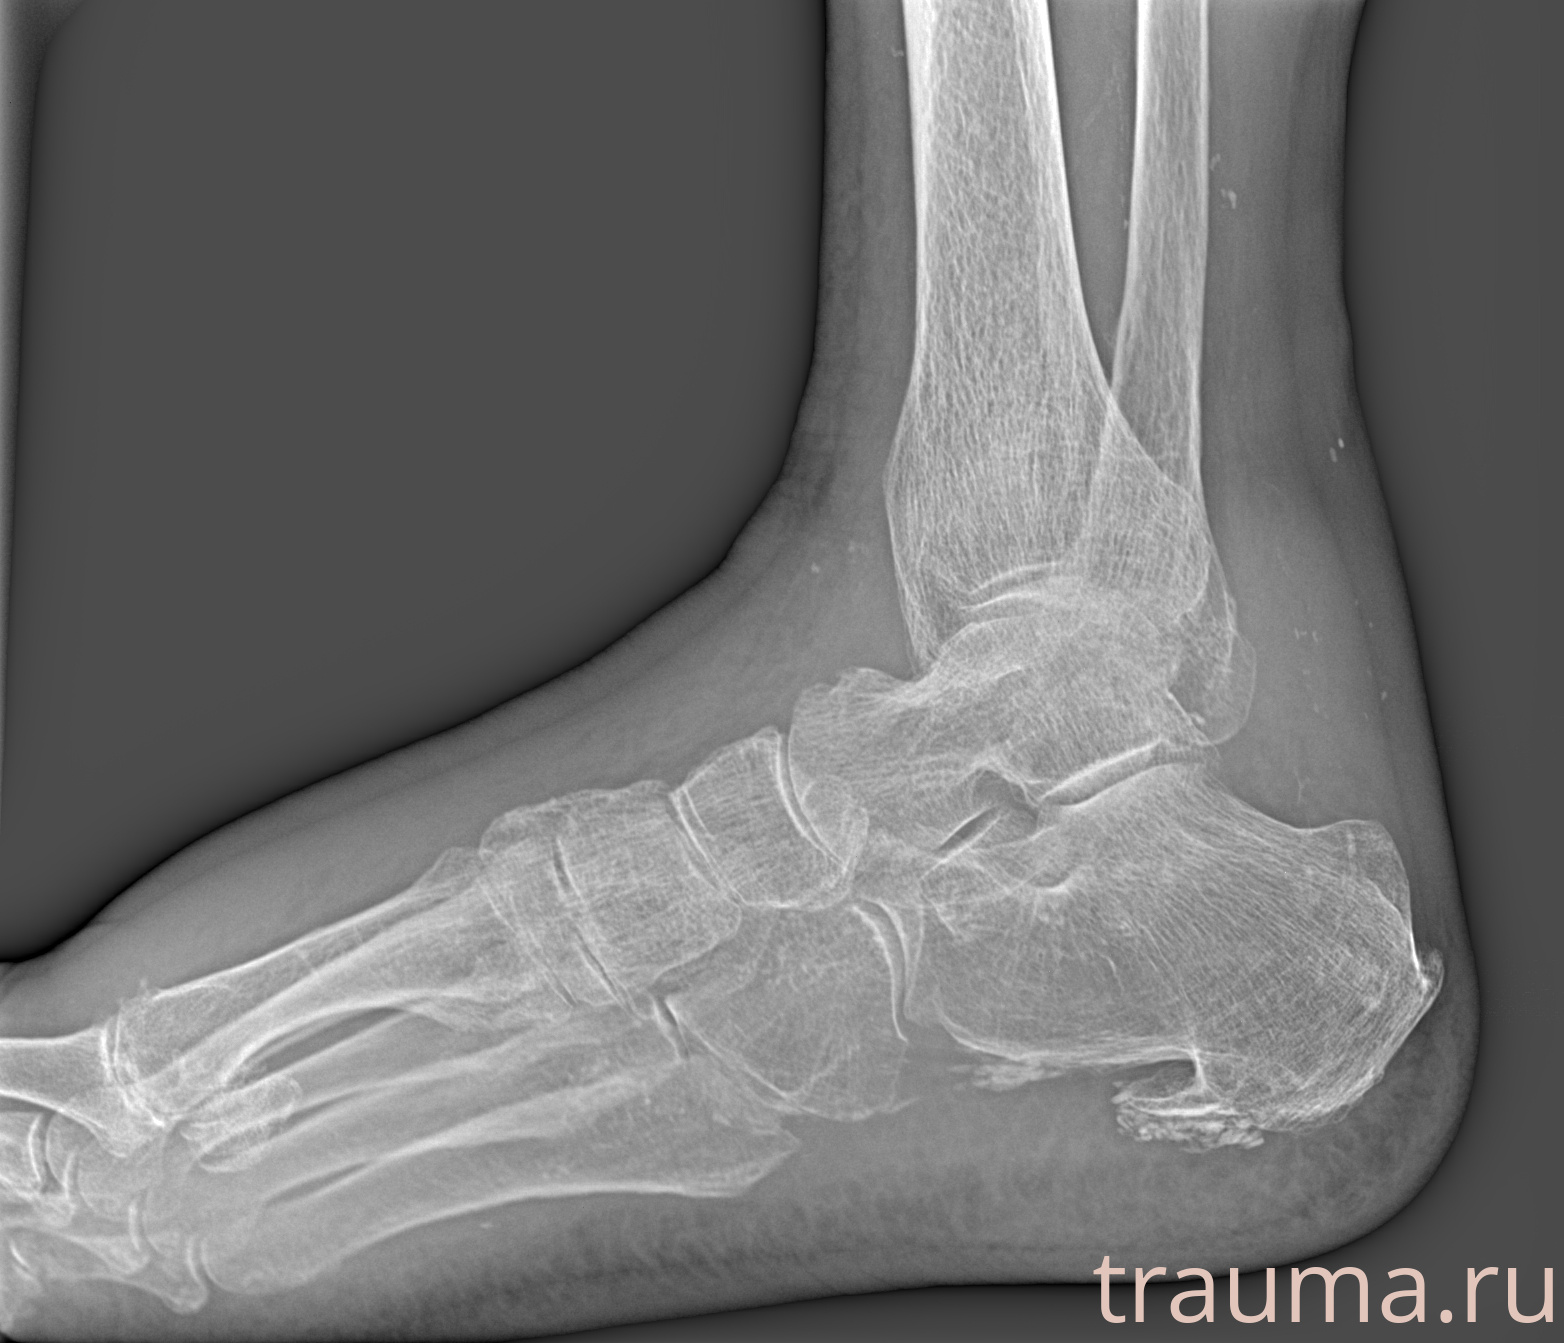

Рентген на дому: по вашему адресу приезжает врач-рентгенолог, травматолог-ортопед с мобильным рентгеновским аппаратом, проводит диагностику травмы или заболевания, делает необходимые рентгенограммы, дает рекомендации по дальнейшему лечению. Получить качественные снимки в домашних условиях возможно благодаря уникальной методике, разработанной МосРентген Центром для института  Склифосовского